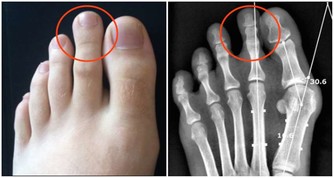

5、冠心病

晚飯吃太晚,未分解掉的血脂易累積在血管壁上,形成動脈硬化,達到一定程度,可能發展成冠心病。